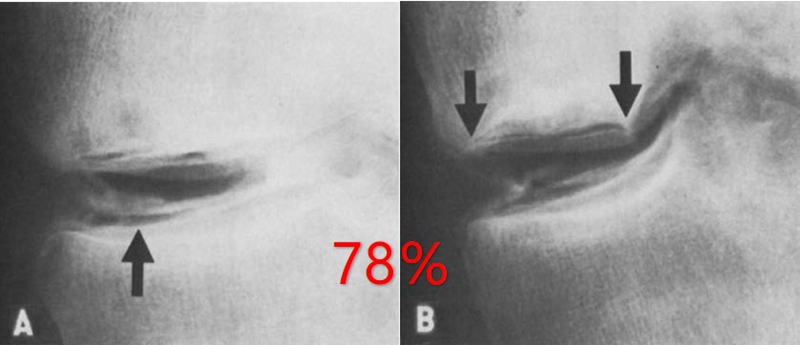

关于SONK与内侧半月板损伤,在一项研究中,关节造影检查27个SONK膝关节中发现有21个(78%)半月板撕裂,半月板碎片边缘的应力集中可能导致股骨髁缺血性坏死。

表明老年患者通过关节造影早期发现内侧半月板撕裂并及时治疗,对于避免“自发性”骨坏死的晚期变化可能很重要。